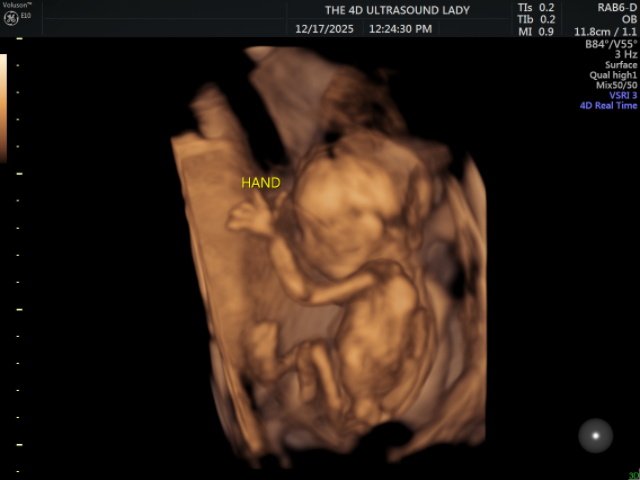

Right after the beach, we traveled to the States to spend Christmas in Alabama. This was the first time in a long while that we were able to truly slow down and rest, and it was very needed. We were exhausted, and that time ended up being incredibly refreshing. We were able to reconnect with our church family, spend lots of time with relatives, and see dear friends. We also found out during this trip that we are expecting another little girl in May, which has been such a joyful thing to celebrate.

- That our baby girl, Presley Kelly, continues to be healthy and that the pregnancy progresses smoothly

Jay, Kelsie, Logan, and Presley